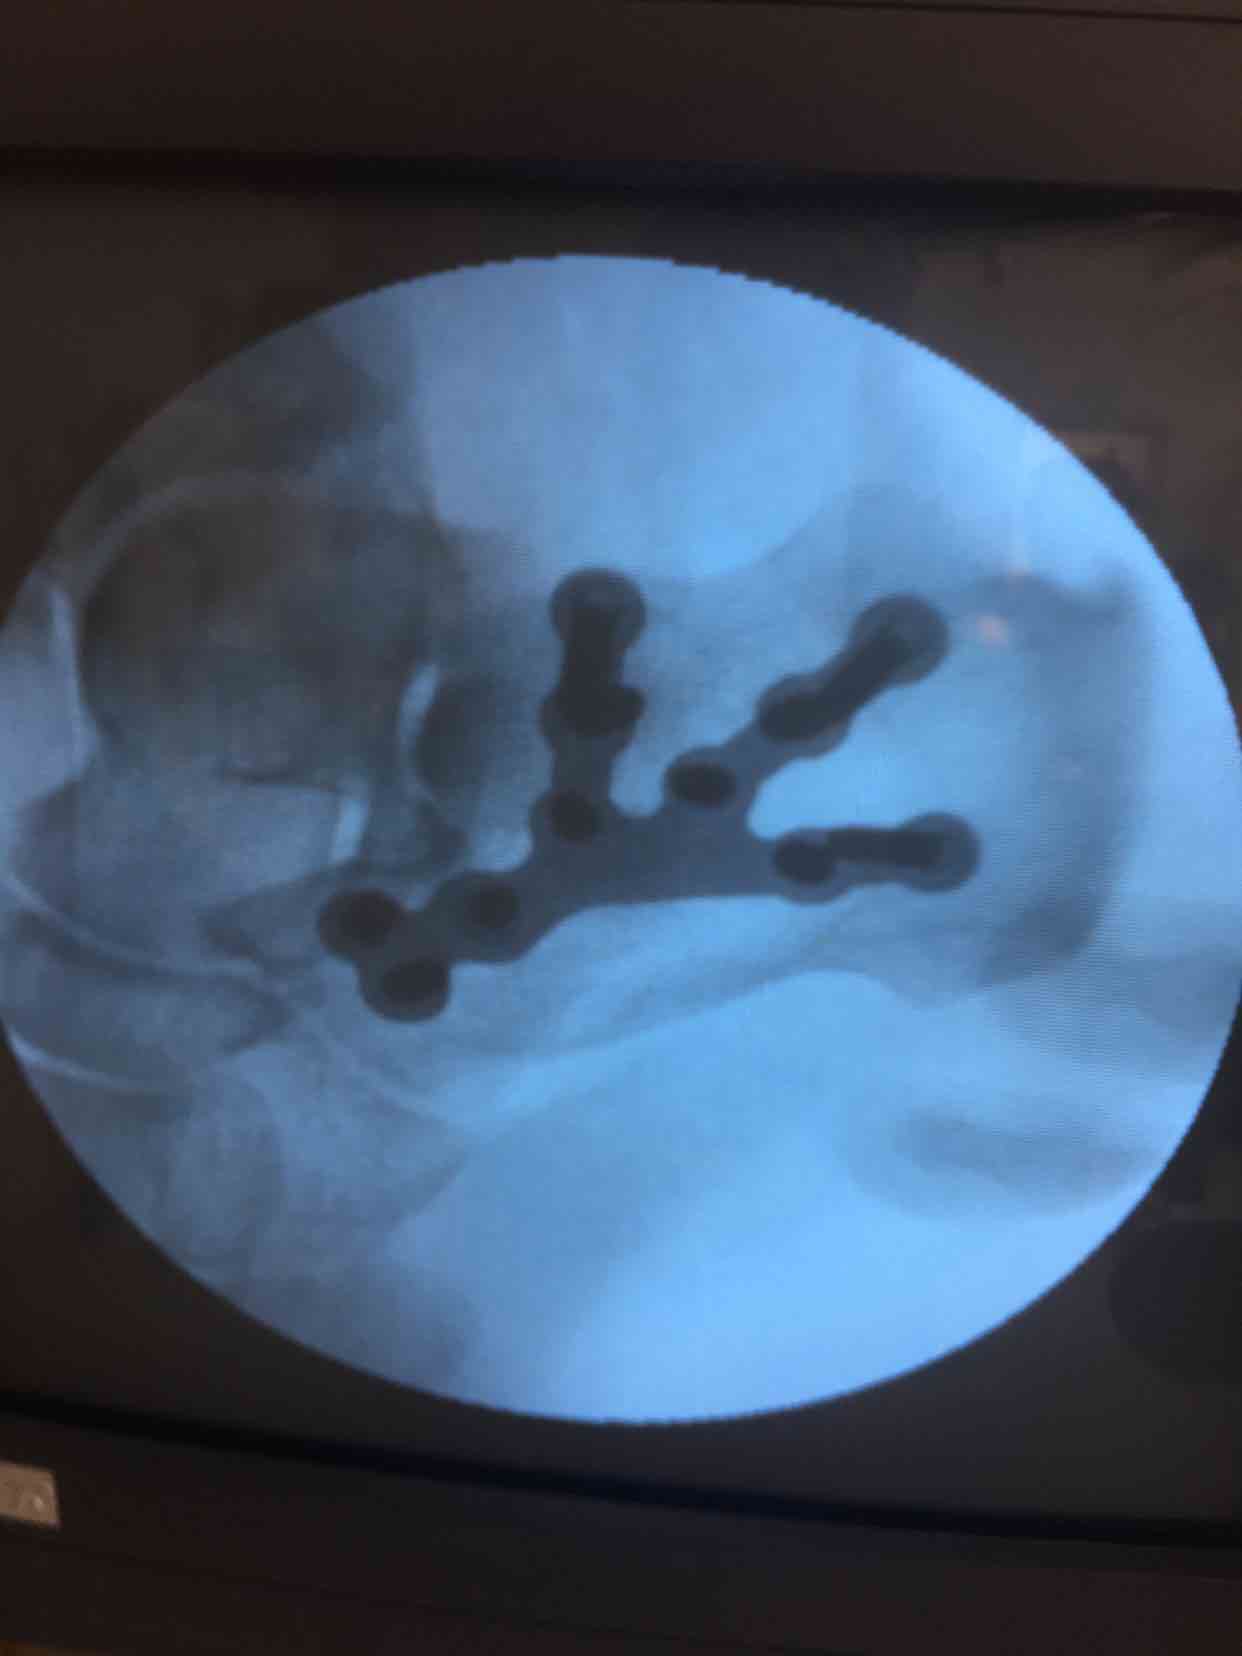

诊断  左跟骨粉碎性骨折完善术前检查,在腰麻下行切复内固定术,术中撬拨复位,选用克氏针临时固定,放置锁定钛板固定,术后抗炎,消肿等处理。